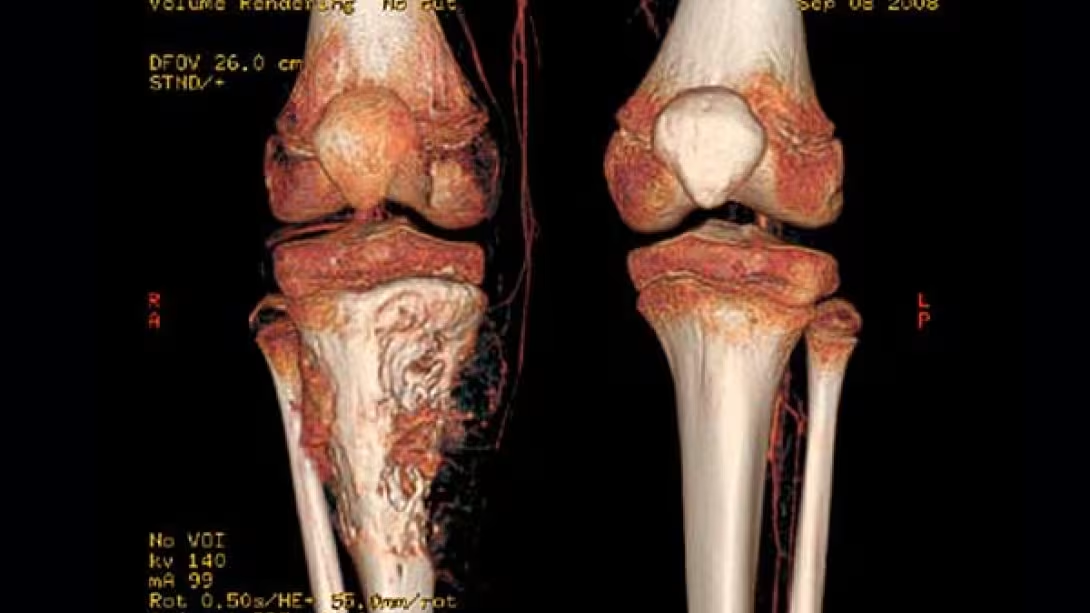

3. Puede aparecer en cualquier hueso del cuerpo, aunque la ubicación más frecuente es alrededor de la rodilla, especialmente en el fémur y la tibia; en el húmero y cerca de la articulación del hombro.